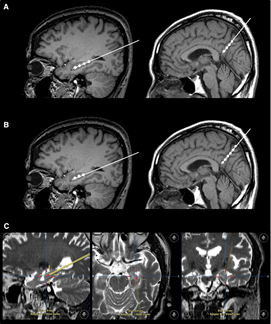

不僅如此,干細(xì)胞輸注治療安全可行。一項(xiàng)“立體定向腦內(nèi)注射人間充質(zhì)干細(xì)胞治療AD病人”的臨床試驗(yàn)結(jié)果表明,在治療結(jié)束后的24個(gè)月隨訪時(shí)間內(nèi),患者沒(méi)有出現(xiàn)與干細(xì)胞治療相關(guān)的嚴(yán)重的不良反應(yīng)。

2023年1月24日,國(guó)際學(xué)術(shù)期刊Movement Disorders (運(yùn)動(dòng)障礙)發(fā)表一篇研究性文章。研究者從胎兒中腦分離制備出多巴胺神經(jīng)祖細(xì)胞,移植到患者的大腦中。設(shè)計(jì)方案:給15名患者(年齡<70歲)注射了三種劑量的細(xì)胞量(4×10*6,12×10*6,40×10*6細(xì)胞),隨后進(jìn)行12個(gè)月的隨訪。研究結(jié)果顯示:低劑量組的運(yùn)動(dòng)能力恢復(fù)效果為11.6%,中劑量組為26%,高劑量組為40%。此外,沒(méi)有副作用,如出血、免疫排斥、炎癥和腫瘤形成。